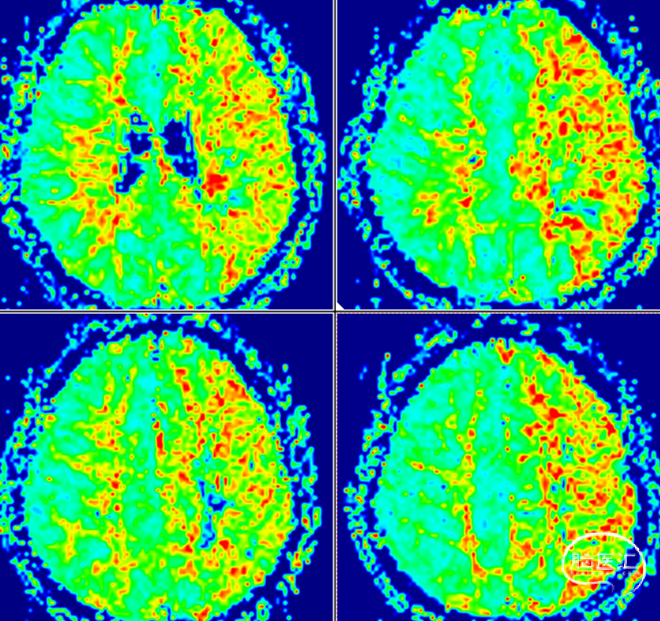

PWI灌注成像:左侧大脑半球低灌注(TTP、MTT明显延长。CBV、CBF减低)。